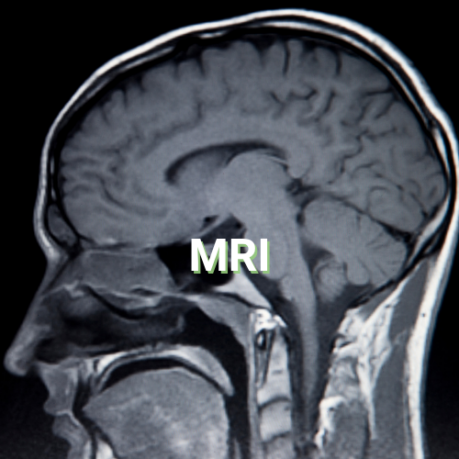

Seeing with magnets

Magnetic resonance imaging, or MRI, uses large magnetic radio waves used to create a detailed, cross-sectional image of internal organs and structures.